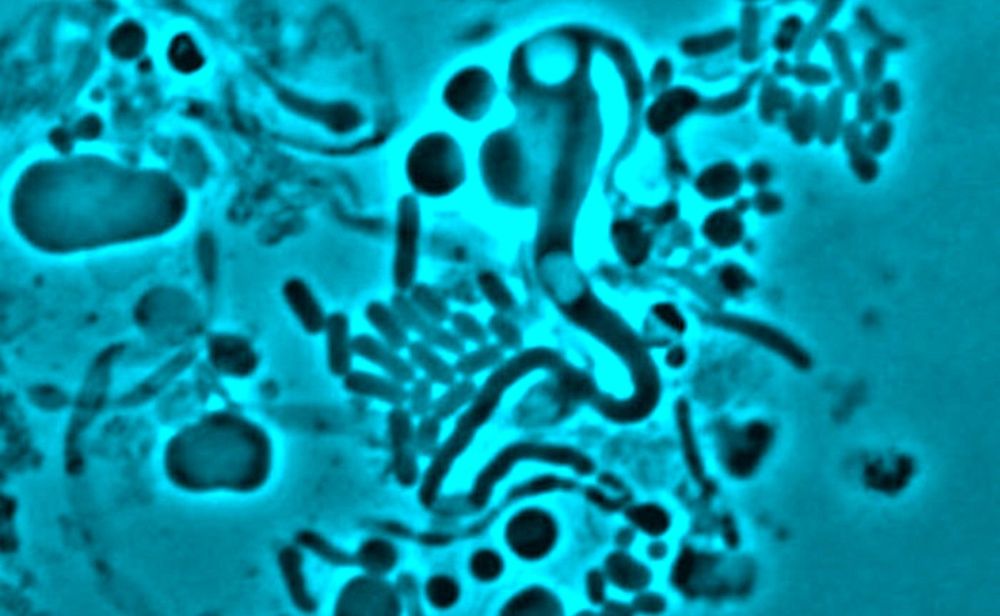

Une bactérie qui survit et se cache malgré une structure fragile

L'étude, qui a impliqué l'utilisation des échantillons obtenus grâce à une collaboration avec des cliniciens du Newcastle Freeman Hospital, organisée par les docteurs Phillip Aldridge et Judith Hall, montre que lorsque des antibiotiques sont présents — comme chez un patient qui reçoit de la pénicilline ou un autre antibiotique visant la paroi cellulaire, les bactéries peuvent se transformer et perdre cette dernière, qui est souvent la cible de ce genre d'antibiotique. [video width="500" height="300" mp4="https://storage.ghost.io/c/ff/1a/ff1a0836-0870-4803-888c-ae1b8c48d937/content/media/2025/04/changement-forme-bacterie-forme-l-resistance-antibiotiques.mp4" poster="https://storage.ghost.io/c/ff/1a/ff1a0836-0870-4803-888c-ae1b8c48d937/content/images/2025/04/potentielle-cause-resistance-antibiotiques-identifiee-1.jpg"][/video] VIDÉO : Cette séquence montre la transition d'une bactérie, sur des milieux osmoprotecteurs, de la forme L à une forme "allongée" (en bâtonnet) après que l'antibiotique a été retiré. Crédits : Université de Newcastle, Royaume-Uni

Dans le cadre de la recherche, il a également été capturé sur vidéo et pour la première fois, des bactéries de forme L isolées d'un patient atteint d'une infection urinaire, qui reformait leur paroi cellulaire après que l'antibiotique ait agit, en seulement 5 heures de temps. L'équipe a également pu montrer par une microscopie directe, que la commutation de forme L est possible dans le contexte d'un organisme vivant entier, et pas seulement dans des conditions artificielles en laboratoire.

Une méthode de détection osmoprotectrice spéciale était nécessaire pour préserver les bactéries de forme L les plus faibles et leur permettre d'être identifiées en laboratoire. Maintenant, l'équipe poursuivra ses recherches avec des essais sur des patients ayant déjà été traités.